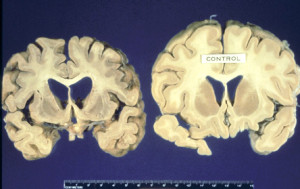

Interagendo con la proteina prionica“sana”, il glicolipide GM1 aumenta le probabilità che assuma la forma “tossica”, causa delle encefalopatie spongiformi...

Un nuovo test del sangue ha mostrato di riuscire a evidenziare proteine malformate che sono legate alla forma umana del...

Una improvvisa perdita di udito da entrambi i lati puo' essere un sintomo del morbo di Creutzfeldt-Jakob, una patologia della...

Nuovi polimeri auto-illuminanti appena sviluppati sono stati progettati appositamente con la capacità di dirigersi su prioni tossici e renderli innocui,...